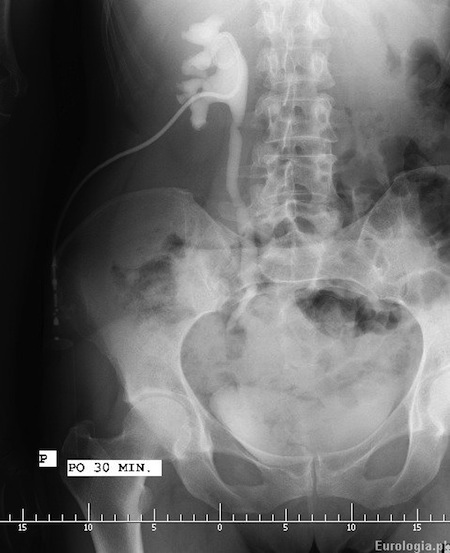

Fot. Pieloureterografia zstępująca wykonana u pacjenta po 30 minutach od podania środka kontrastującego do drenu nefrostomijnego. W opisywanym przypadku dren nefrostomijny założony był kilka tygodni wcześniej z powodu roponercza w przebiegu kamicy prawego moczowdu - złóg tuż poniżej prawego stawu krzyżowo - biodrowego.

Ureteropielografia zstępująca polega na wykonaniu zdjęcia przeglądowego nerek i pęcherza po podaniu środka kontrastującego przez cewnik nefrostomijny założony do układu kielichowo - miedniczkowego nerki. Badanie stosowane u pacjentów z założoną wcześniej nefrostomią pomaga uwidocznić lokalizację i rodzaj przeszkody w odpływie moczu z nerki.

Ureteropielografia zstępująca jest badaniem dobrze znoszonym przez pacjentów. Badanie jest niebolesne, czasami pacjenci zgłaszają chwilowe pobolewanie okolicy lędźwiowej w momencie podawania kontrastu. W przypadku wątpliwości diagnostycznych urolog pozostawia zamknięty dren nefrostomijny i zleca późne zdjęcia rentgenowskie celem oceny spływu zakontrastowanego moczu.